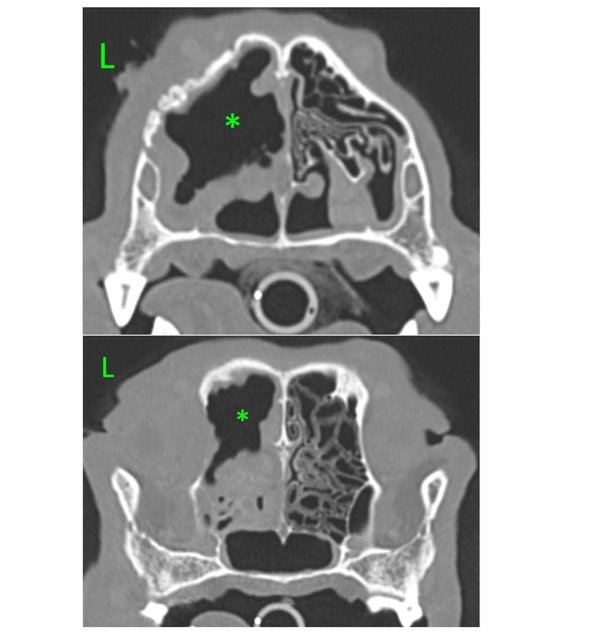

Стали искать куда вывозить на доп. обследование - сдали кровь в приюте и 17 июля вывезли в ИВЦ на прием. Нам выдали заключение и мы даже успели сделать КТ. Фромма вернули в приют, результатов КТ надо было ждать около 3-х дней. Мы за ним наблюдали и ждали.

Завтра, 1 августа, везем Фромма еще раз в клинику В добрые руки, ему нужно будет делать санацию и чистку с лекарством. Просто таблетки не помогают, к сожалению, его ситуация уже запущенная, и мы это понимали. Просто не делают такие процедуры, пока все анализы не придут. Ему фактически не лучше. Если честно, мы не хотим подробно описывать его заболевание и возможные причины его получения. Это сильно выбивает нас из колеи, а нам надо заниматься его здоровьем.

16 августа Фромм поехал на процедуру с лекарством Клотримазол к Дудочкину. Но доктор, осмотрев и выслушав наши пояснения относительно его самочувствия, отказал в процедуре без дополнительного КТ из-за опасности попадания лекарства сразу в головной мозг. Клотримазол мы купили 986 р. + еще 1153 р. таблетки которые он принимает. Минус темы 2139 р.

| По итогам КТ назначены антибиотики. Купили, ушли еще в минус 4134 р. Процедуру можно проводить, так что скоро Фромм снова поедет на очередное испытание.